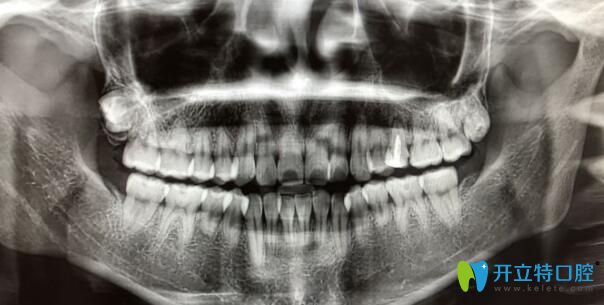

一些朋友們因?yàn)檠例X排列不整齊或形態(tài)異常想要進(jìn)行矯正,在拍片檢查時被告知牙根較短,可能不適合進(jìn)行正畸治療。滿懷矯正決心的你,或許又嘗試咨詢了另一家診所,這次醫(yī)生表示可以進(jìn)行正畸。面對這樣的情況,你是否感到困惑,不知所措?今天,我們將深入探討牙根短的人是否適合佩戴牙套,并分享一些牙根短者進(jìn)行正畸后的實(shí)際情況。

1、牙根特別特別短

其實(shí)牙根短也是分情況的,如果是牙根特別短,你面診了三四家,都別醫(yī)生拒絕,醫(yī)生告訴你如果你做了矯正,很可能還沒有做完,牙根短的牙齒就有脫落的風(fēng)險,那么建議你還是不要做正畸為好。

2、牙根稍微有點(diǎn)短

一般這種情況,有些醫(yī)生根據(jù)自己的經(jīng)驗(yàn)會建議你不要做矯正。有些醫(yī)生會告訴你可以做矯正,但是矯正的速度會比一般人慢,別人矯正花費(fèi)1-2年,你可能需要3-4年,并且風(fēng)險是很大的,確實(shí)有掉牙的風(fēng)險,如果自己能接受可能存在的風(fēng)險,還是可以做的。